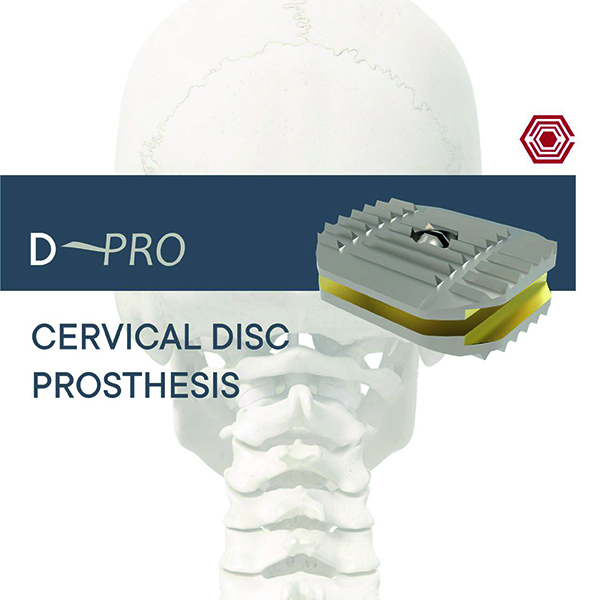

D-Pro

Akif Kaya Aybek

Norm Akademi

- Surgical Tecjnique

- Kinematics

- Materials Anatomical Angles

- Sizes

- Instruments Container

- Instrument Types